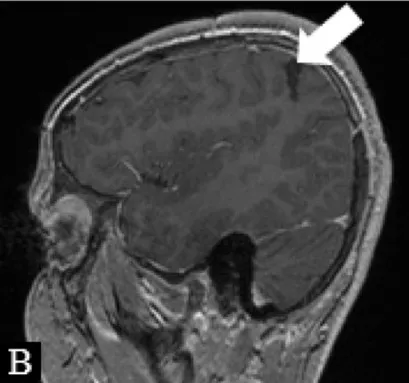

| Surgery: Modified hemispherotomy after intra-operative monitoring (IONM) and preservation of the right leg motor function (early sagittal CT showing the descending fibers from that area, white arrow on Figure B). | |||

| Follow-up: Early postoperative seizures for 1 week, then >1 year seizure-free. | |||